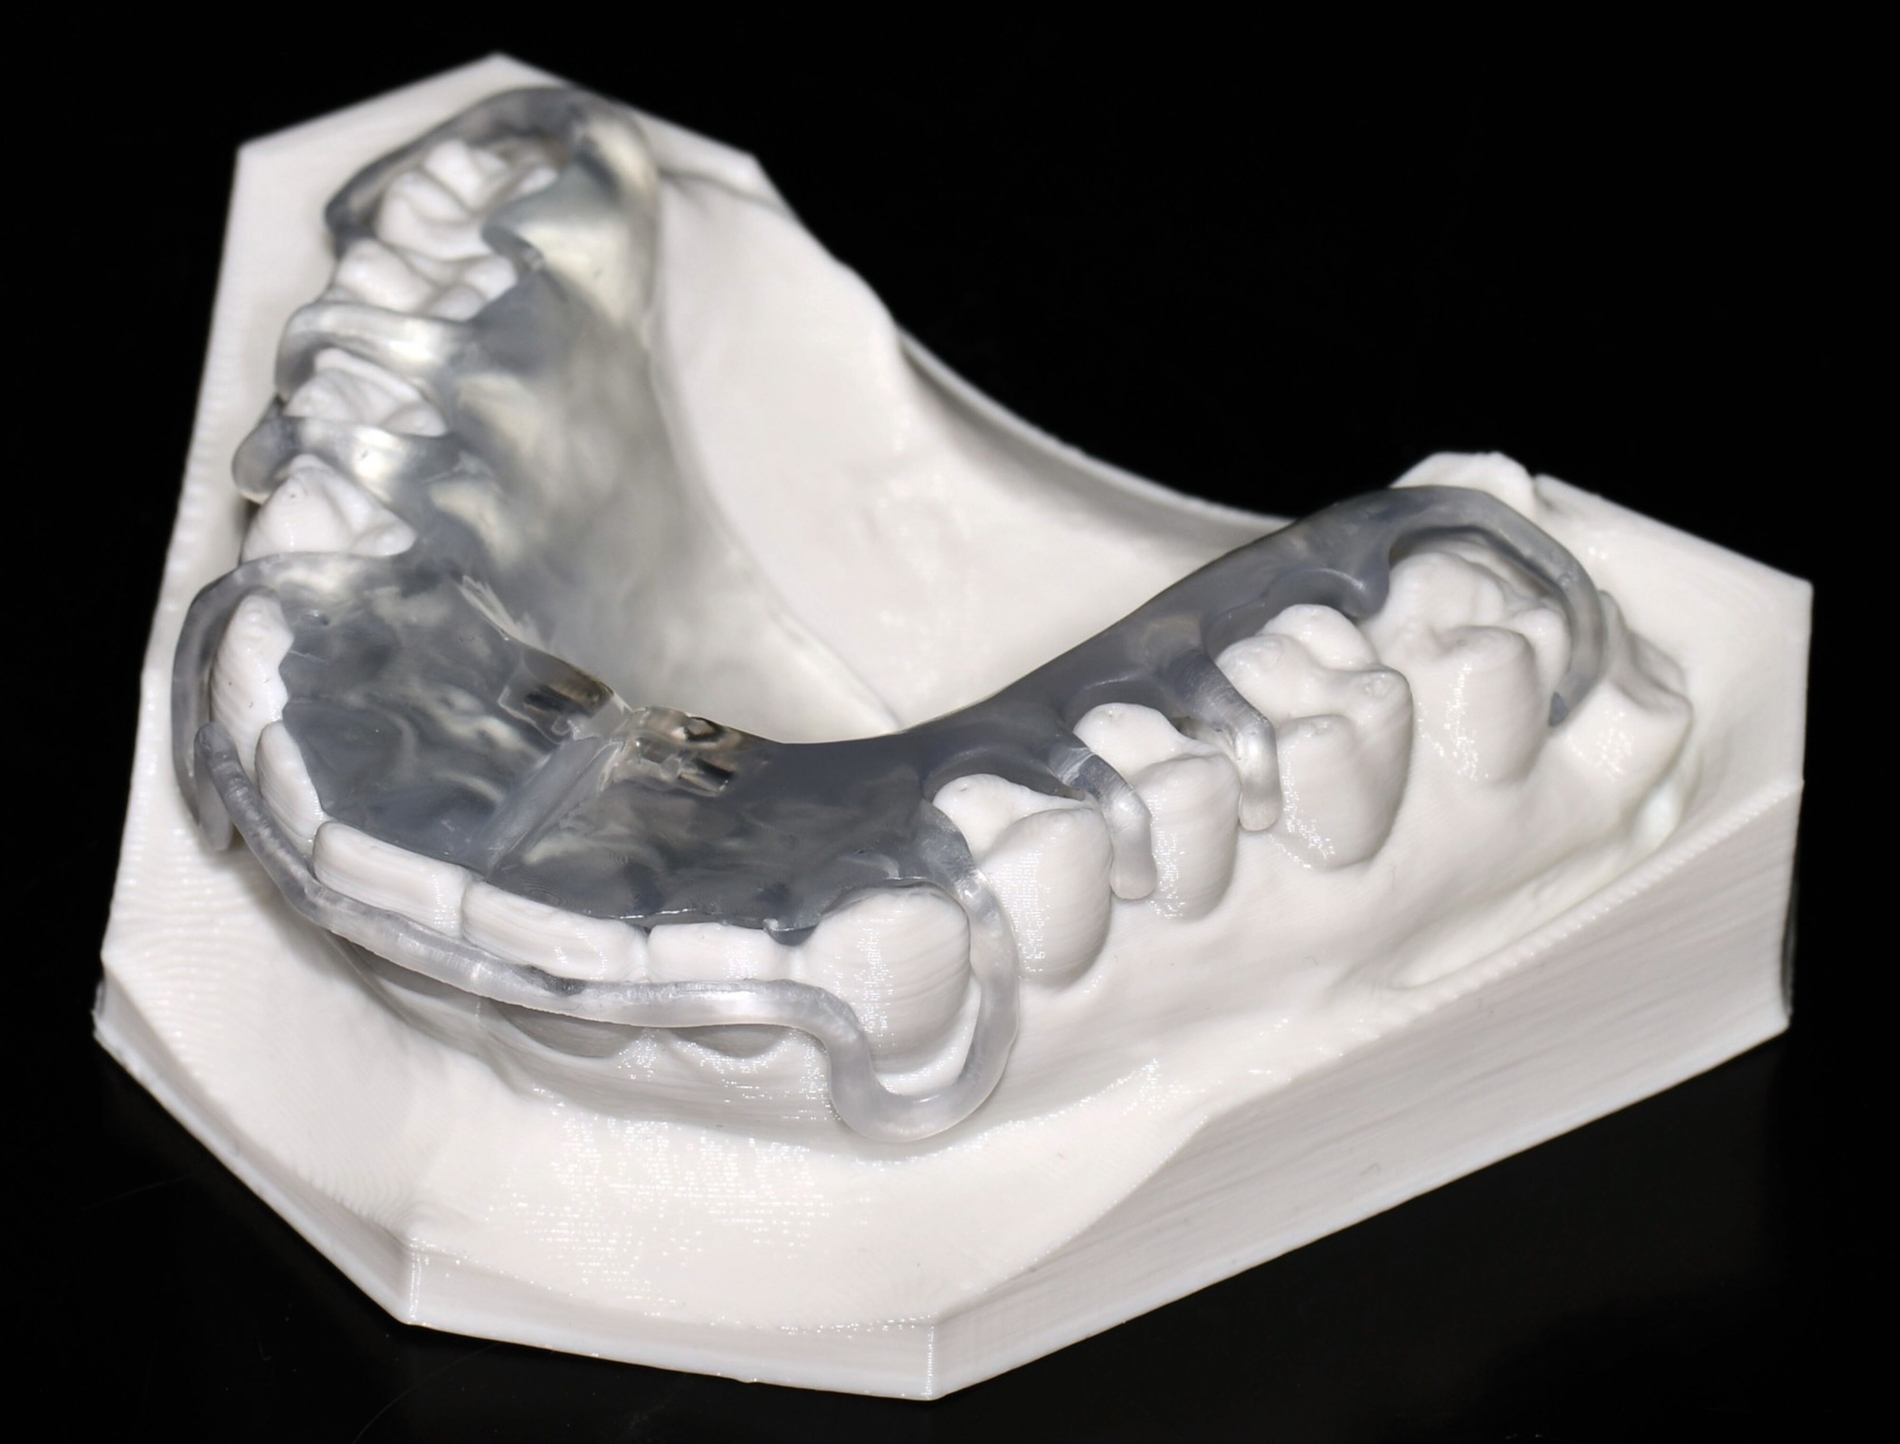

Herausnehmbare Apparaturen

Als hochinnovatives Feld hat sich auch die Herstellung herausnehmbarer Apparaturen im 3-D-Druck entwickelt (Abbildung 4), beschränkt sich jedoch noch auf einzelne Forschungsansätze [Al Mortadi et al., 2012; van der Meer et al., 2016; Graf et al., 2022; Keller et al., 2022]. Intensiv an neuen Konzepten in der Herstellung 3-D-gedruckter herausnehmbarer Apparaturen wird am Universitätsklinikum Heidelberg geforscht. Da herausnehmbare kieferorthopädische Apparaturen im Regelfall bei jungen Patienten eingesetzt werden, kommt dem Vorteil einer unbegrenzten Replikation und einer kostengünstigen und schnelleren Herstellung ein besonderer Stellenwert zu.

Im Unterschied zu konventionellen Apparaturen bestehen die 3-D-gedruckten Apparaturen vollkommen aus Kunststoff. Eine Einarbeitung metallischer Elemente nach dem 3-D-Druck ist möglich [Al Mortadi et al., 2012; Al Mortadi et al., 2024], erfordert jedoch zusätzlichen Zeitaufwand. Zur Herstellung herausnehmbarer Apparaturen eignen sich konventionelle praxisinterne 3-D-Stereolithografie-Drucker, die in vielen Fällen bereits im regulären Praxisalltag zum Modelldruck verwendet werden. Die verwendeten Kunststoffe sollten dabei eine Klasse-IIa-Zertifizierung aufweisen, so dass ein sicherer langfristiger intraoraler Einsatz der Apparatur gewährleistet ist. Weiter muss die Apparatur nach dem 3-D-Druck gemäß den Herstellerangaben nachprozessiert werden. Im Regelfall beinhaltet dieser Prozess ein Waschen in Isopropylalkohol (IPA) sowie eine Nachhärtung im Lichthärtegerät. Eigens durchgeführte Studien sowie die bisherige klinische Erfahrung bestätigen eine hohe mechanische Stabilität, eine hohe Passgenauigkeit sowie eine breite Akzeptanz der Patienten [Roser et al., 2021; Roser et al., 2023; Segnini et al., 2023]. Des Weiteren wecken die 3-D-gedruckten Apparaturen bei den meist jungen Patienten großes Interesse, was wiederum die Trage-Compliance unterstützt. Durch weitere Entwicklungen im 3-D-Druckbereich wird zukünftig auch ein Farbdruck möglich werden.